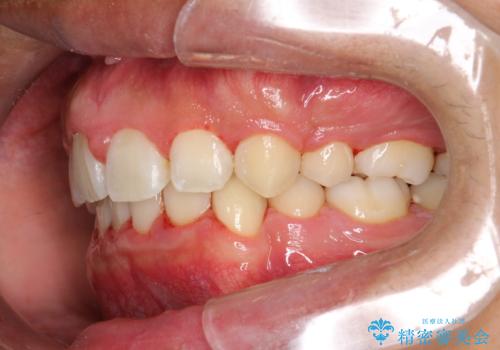

ワイヤー矯正終了時に装置除去と合わせてPMTC

- ワイヤー矯正の終了時にしばらく行っていないためクリーニングも希望されました。装置の除去j時にPMTC60分コースを行いました。

装置を除去すると、エナメル質にダメージがかかることなどがあります。除去の際、一緒にクリーニングを行うことで、エナメル質をなめらかにしたり、歯ぐきの引き締まりが見られます。また、歯ブラシだけでは取り除けない汚れも取り除きますので、歯の表面がツルツルになります。矯正治療中・終了時には合わせてPMTCを行うことがおすすめです。